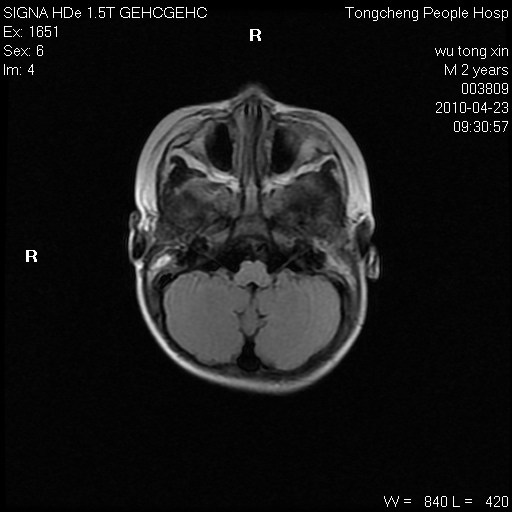

以下是引用赵物学在2010-4-25 12:43:00的发言:[br]巨脑回[br]侧脑室后角低密度影考虑hie或肾上腺脑白质营养不良?[br][br][本贴已被 赵物学 于 2010-4-25 12:51:28 修改过]

以下是引用gaoxiao在2010-4-25 16:54:00的发言:[br]巨脑回畸形。脑白质髓鞘化不良

以下是引用pujunzhi在2010-4-25 21:35:00的发言:[br]考虑 1双侧大脑皮质发育不良 2轻度脑积水 3双侧脑室后角旁片状长t1长t2信号,需继续观察,因为正常小儿此处脑白质的髓鞘化时间可以延迟到4-6岁,才显示正常。